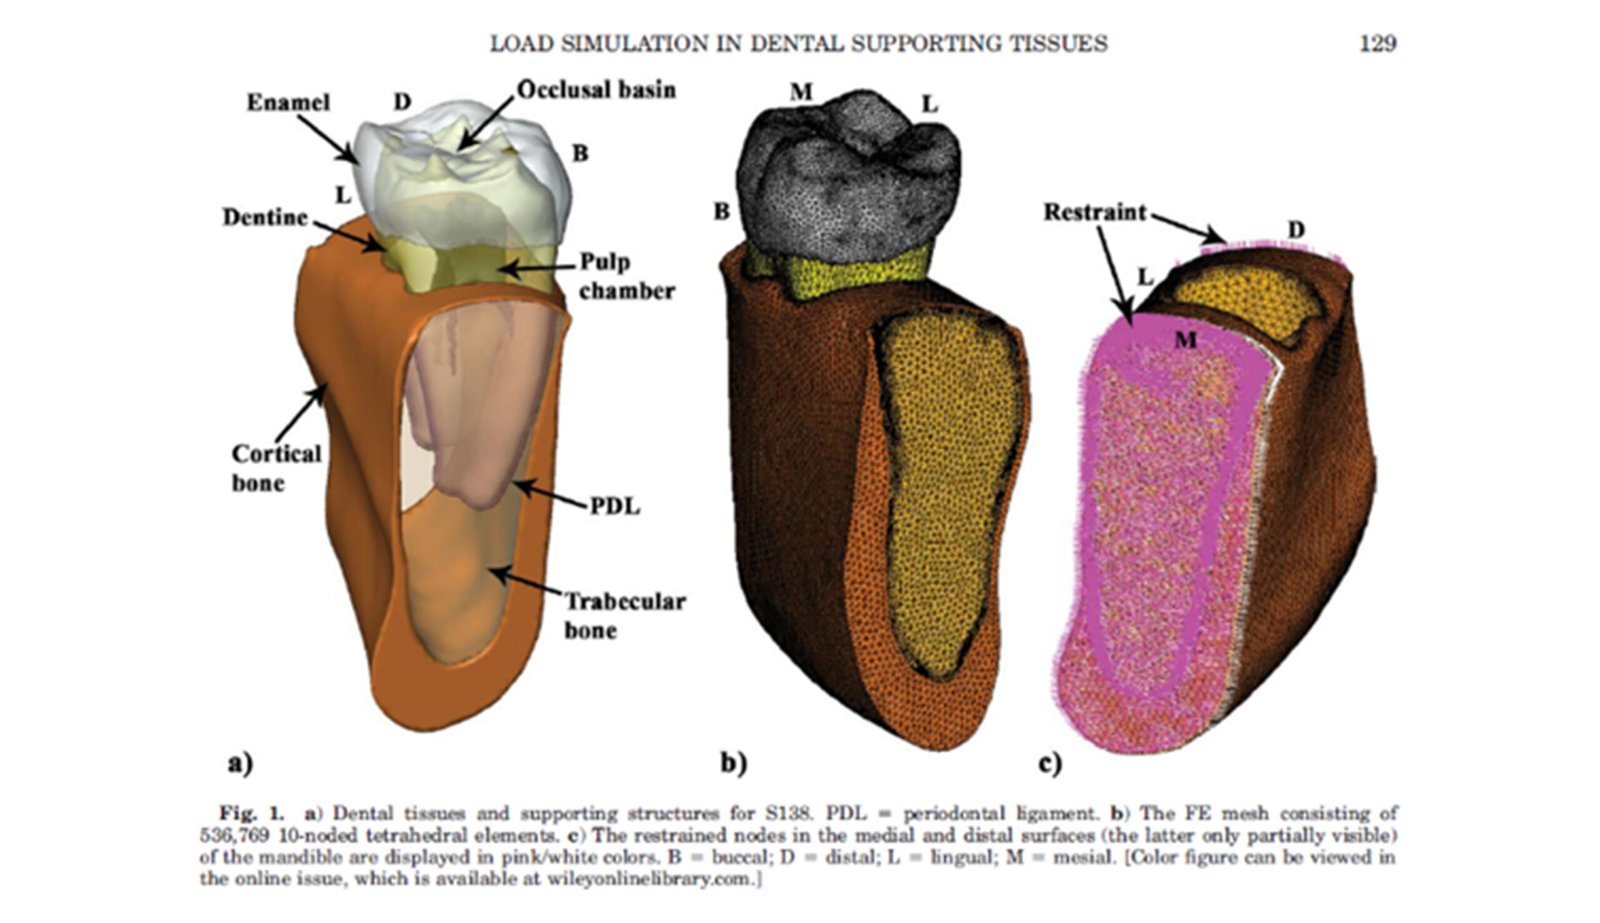

The Endodontic FEA section evaluates the biomechanical performance of root canal–treated teeth, endodontic tools, and reinforcement strategies. Through precise material characterization and micro-CT–based superimposition, we assess fracture risk, stress pathways, and instrument fatigue under various clinical scenarios. These simulations guide the selection of safer instrumentation techniques and restorative strategies. Our goal is to enhance predictability and reduce procedural complications.